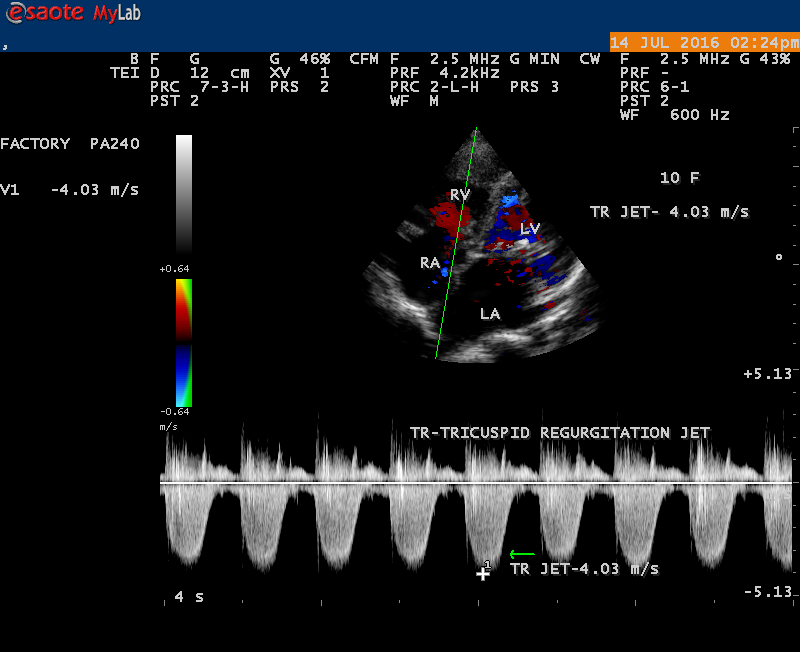

The severity of eccentric MR is underestimated because of coanda effect. If the regurgitant jet area fills < 20> 40% indicate severe regurgitation. The vena contracta ( the neck or narrowest portion of the jet), typically imaged perpendicular to the commissural line in parasternal long axis and apical four chamber views is well defined in both central and eccentric jets, but not in chaotic, disorganized jets due to flail leaflets. Its width < 3> 7 mm defines severe MR and a mean value of > 8mm indicates severe functional MR. The flow convergence method based on PISA (proximal isovelocity surface area) may not applicant for eccentric and multiple jets or complex and elliptical regurgitant orifices to assess the severity of mitral regurgitation.. The adaptation of LV to the increased volume overload is reflected by LV dimensions and ejection fraction.. In chronic compensated phase, the forward stoke volume is maintained through an increase in LV ejection fraction >65% and the patient could be asymptomatic. In chronic decompensated phase of MR, the forward stroke volume decreases and the LA pressure increase significantly. The patient may be still asymptomatic and the LV ejection fraction may be in the low normal range despite the presence of significant muscle dysfunction. The contractile function decreases silently and become irreversible. In the current guidelines, surgery is recommended in asymptomatic patients with severe organic MR when the LV ejection fraction is ≤ 60%. However, in acute stage, the LV ejection fraction increases in response to the increased preload. The end-systolic diameter is less preload dependent than the ejection fraction and it may be more appropriate to monitor the global LV function. The end-systolic diameter > 45 mm also indicate the need for mitral valve surgery [43]. In this child, the LVESD (end-systolic diameter) is 30.7 mm and the ejection fraction (EF) is 66% as shown in Figure 19. New parameters are currently available for a better assessment of LV function. A systolic tissue Doppler velocity measured at the lateral annulus <10>40-50mm) may predict the onset of atrial fibrillation and poor prognosis in patients with organic MR[48]. The excess regurgitant blood entering in the LA may induce acutely or chronically a progressive rise in pulmonary pressure and the presence of TR (tricuspid regurgitation) as shown in Figures 26 and 28 permits the estimate of systolic pulmonary arterial pressure and mitral valve surgery is recommended when it is > 50 mmHg at rest and LA reverse remodeling may occur after surgery. The severe TR may cause a decrease in hepatic vein systolic velocity and systolic flow reversal may occur as shown in Figure 32 and its sensitivity is 80% [49]. The TR (tricuspid regurgitation) jet velocity in this child is 4.03 m/s as shown in Figure 28 which corresponds to a systolic pulmonary artery pressure of 65 mmHg.